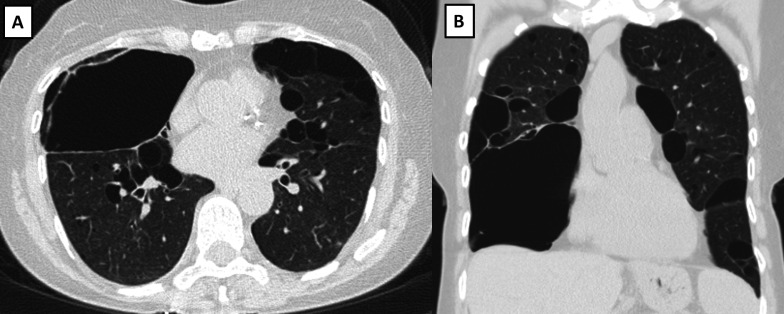

Results: Among 82 patients with BHD aged 50 years or older, 49 (59%) were female and the median age was 57 years (range, 50-79) at baseline. Pneumothorax occurred in 46 patients (56%). Lung cysts were observed on CT in 77 patients (94%) and were bilateral in nearly all cases. The number of cysts was≥10 for most patients (84%) and the median size of the largest cyst was 31 mm (range, 4-160 mm). Median (range) % predicted values of forced vital capacity, forced expiratory volume in 1 s and diffusion capacity of the lung for carbon monoxide were 98 (62-147), 92 (56-145) and 85 (61-133), respectively, for those with data available. During follow-up (median, 41 months; range, 3-259), 35% of patients manifested worsening in pulmonary function or cystic lung disease.

Abstract Image